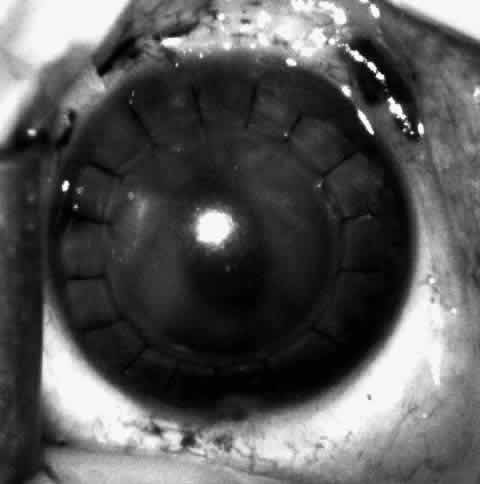

Children who have traumatic cataracts with corneal lacerations are well served by this procedure because the injury often destroys the capsular support that can be used to stabilize an intraocular lens.16–18 The epikeratophakia graft provides structural support for the weakened cornea and minimizes the induced irregular and regular astigmatism, in addition to correcting the optical error (Figs. 3 AND 4).

Fig. 4. Same patient as in Figure 11, with epikeratophakia lenticule in place 3 months after surgery. (Morgan KS, Ellis GS, Marvelli TL, Arffa RC: Epikeratophakia in children. with traumatic cataracts. J Pediatr Ophthalmol Strabismus 23:108–113, 1986)